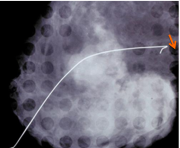

| 09:25, 7 בספטמבר 2012 | Coreneedle1612.png (קובץ) |  |

212 קילו־בייטים | Motyk | 1 | |

| 09:51, 7 בספטמבר 2012 | Coreneedle2712.png (קובץ) |  |

142 קילו־בייטים | Motyk | 1 | |